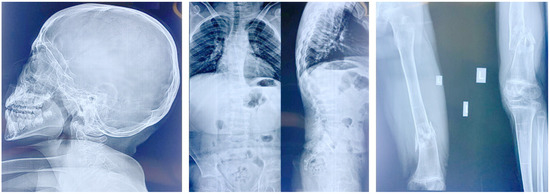

3.1. Clinical Presentations